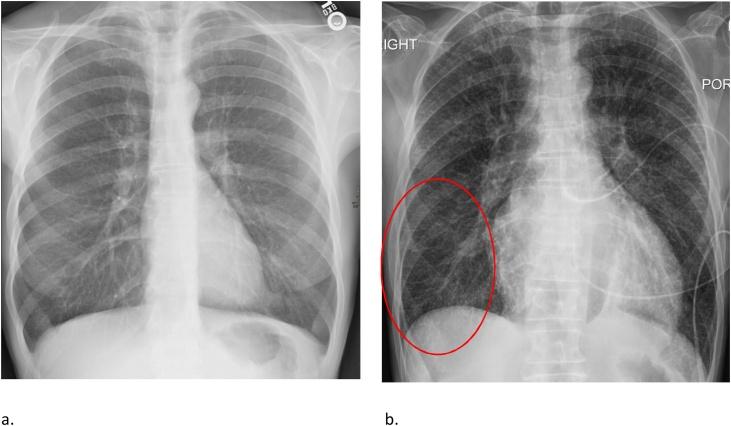

肺水肿:影像学表现及疾病机制的当前认识的图文综述

Pulmonary Edema: A Pictorial Review of Imaging Manifestations and Current Understanding of Mechanisms of Disease.

Pulmonary edema is a common clinical entity caused by the extravascular movement of fluid into the pulmonary interstitium and alveoli. The four physiologic categories of edema include hydrostatic pressure edema, permeability edema with and without diffuse alveolar damage (DAD), and mixed edema where there is both an increase in hydrostatic pressure and membrane permeability. As radiographic manifestations and etiologies are varied, an appreciation for both the common and uncommon manifestations and causes of pulmonary edema is essential for accurate diagnosis.

摘要

肺水肿是一种常见的临床病症,由液体向肺间质和肺泡的血管外移动所致。水肿的四种生理类型包括静水压性水肿、伴有或不伴有弥漫性肺泡损伤(DAD)的通透性水肿,以及静水压和膜通透性均增加的混合性水肿。由于影像学表现和病因各不相同,了解肺水肿的常见和不常见表现及病因对于准确诊断至关重要。